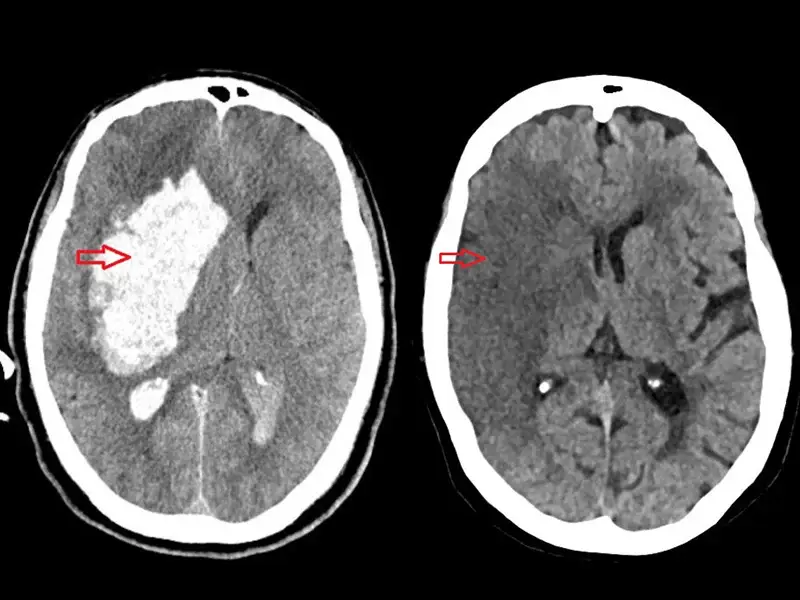

AVC mata um brasileiro a cada seis minutos, apontam registros oficiais

Entre janeiro e outubro, mais de 64 mil pessoas morreram em decorrência da doençaO Acidente Vascular Cerebral (AVC) mata um brasileiro a cada 6 minutos. A informação é baseada em estimativas do Portal da Transparência dos Cartórios de Registro Civil.

64.471 pessoas morreram em decorrência de AVC, o que equivale a um óbito a cada seis minutos. No ano de 2024, foram 85.457 mortes causadas pelo AVC, número que mantém o Brasil entre os países com maior carga da doença.